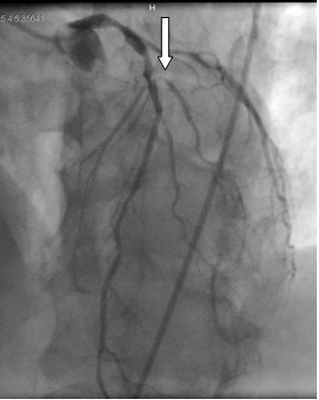

В связи с наличием тяжелой дыхательной и сердечной недостаточности больной выполнялась искусственная вентиляция легких и постоянное внутривенное введение препаратов с положительным инотропным действием. C целью поддержки гемодинамики выполнялась внутриаортальная баллонная контрпульсация. По экстренным показаниям была выполнена коронарография, при которой установлен правый тип коронарного кровообращения, окклюзия 1-й диагональной ветви, стеноз проксимального отдела 2-й диагональной ветви на 60% и гемодинамически незначимые стенозах в бассейне правой коронарной и передней нисходящей артерий (рисунок 6).

Рисунок 6. Данные коронарографии: окклюзия 1-й диагональной ветви левой коронарной артерии (отмечено стрелкой).

Попытка реканализации 1-й диагональной артерии была неуспешной.